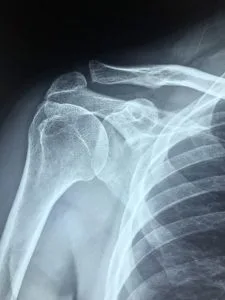

- Skuldra har vært ute av ledd (Alle førstegangsluksasjoner skal tas røntgen av)